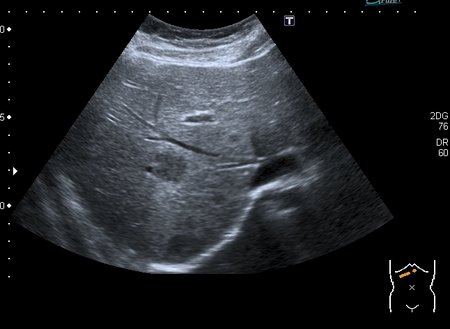

Девочка 13 лет, в течение 2-х недель температура до 38, СОЭ - 40 мм\ч, СРБ - 30.

На УЗИ: Учитывая клинику, лабораторные данные поставил гистиоцитарную инфильтрацию печени и селезёнки при генерализованной инфекции. Несколько раз встречался со схожими случаями, на фоне антибиотикотерапии изменения уходили. Но в данном случае девочка уже получала антибиотики в течение недели, на этом фоне не получено ни клинического , ни лабораторного улучшения, а на УЗИ очаги стали больше. Нужно ли расширять дифференциально -диагностический ряд? Ваши мнения

Имхо, по УЗ-семиотике - множественные небольшие абсцессы.

В наше время тактика ведения абсцессов немного изменилась - крупные абсцессы (более 3 см в диаметре) дренируют, мелкие (менее 3 см) лечат антибиотиками.

Девочка уехала на консультацию в республиканский центр онкогематологии

, результат узнать не удалось.